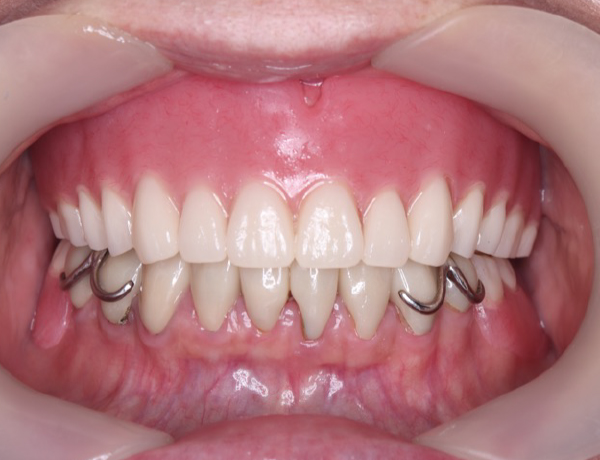

お口の中

上あご

お口の中に入っても、金属の部分がだいぶ広くとってあるのが分かるかと思います。口蓋隆起と言われる骨の部分が当たると痛みが出るので、少しその部分はリリーフして隙間を与える工夫もしています。

入れ歯が割れたり壊れたりする患者さんの多くは、骨が隆起しており、見るからにかむ力が強そうだな!という印象があります。それらを考慮して壊れない入れ歯を作製する必要があるので、今回は、保険ではなく保険外の入れ歯を選択しました。

下あご

左右のかみ合わせも非常にバランス良く噛ませています。また、バネの部分を上の歯が噛み込まないように工夫をしています。良くこのバネの部分で折れてしまう場合がありますので、それを考慮してあります。